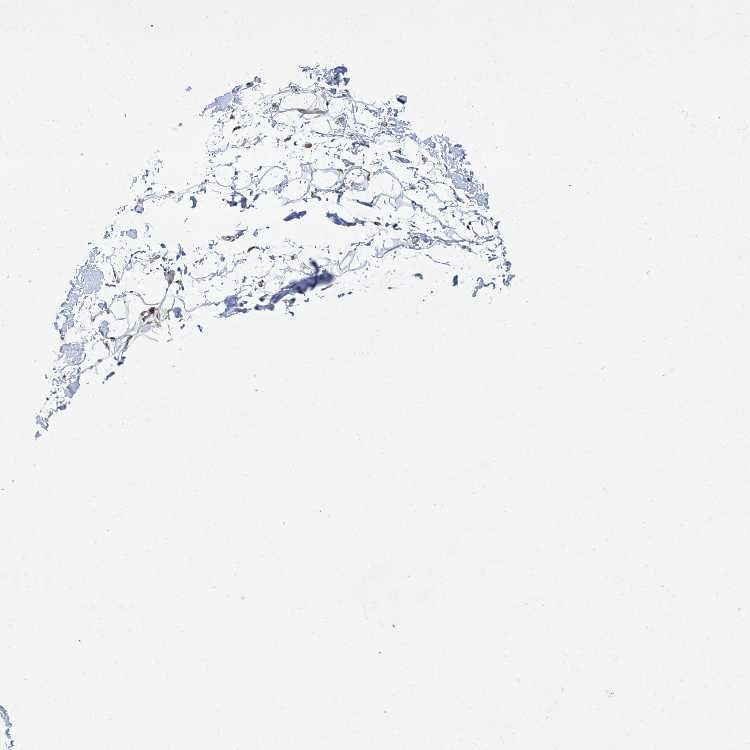

SOFT TISSUE 1 - Antibody stainingi

Antibody staining in the annotated cell types in the current human tissue is reported as not detected, low, medium, or high, based on conventional immunohistochemistry profiling in selected tissues. This score is based on the combination of the staining intensity and fraction of stained cells.

Each image is clickable and will lead to virtual microscopy that enables deeper exploration of all samples and also displays staining intensity scores, fraction scores and subcellular localization as well as patient and tissue information for each sample.

Antibody HPA030813Antibody CAB032306

Chondrocytes Not detectedNot detected

Fibroblasts MediumMedium